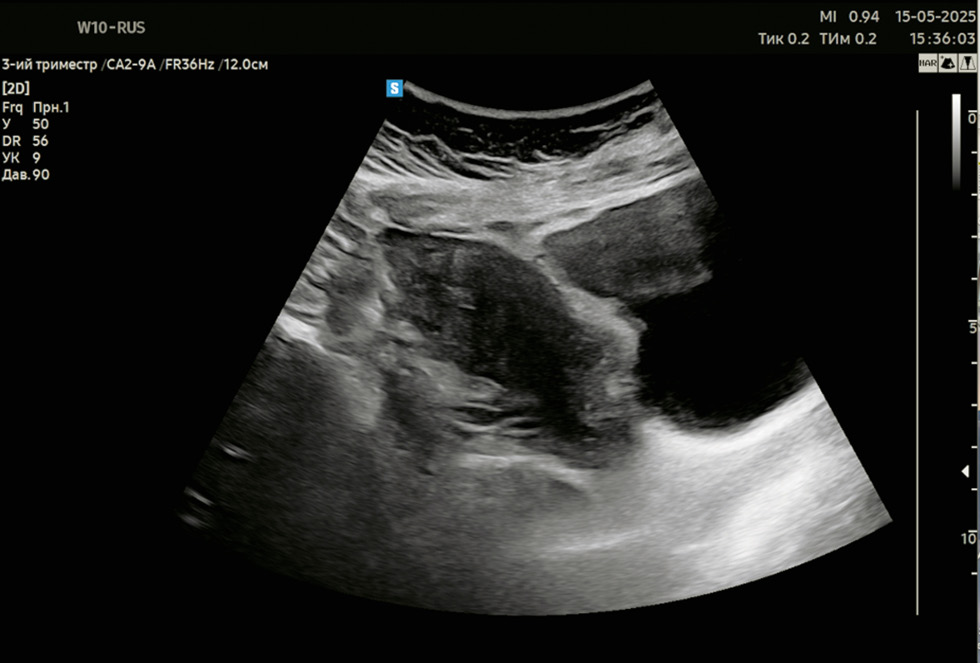

- Изменения в структуре брюшины и контурах органов: локальное утолщение париетальной брюшины и/или контура смежных органов, сопровождающееся повышением эхогенности (рис. 1, 2).

Рис. 2. Формирование ниши. 2 мес. после операции кесарева сечения.

Fig. 2. Uterine niche. 2 months after a caesarean section.

Кроме того, признаками спаечного процесса могут быть деформация стенок мочевого пузыря, формирование ниши в области послеоперационного рубца.